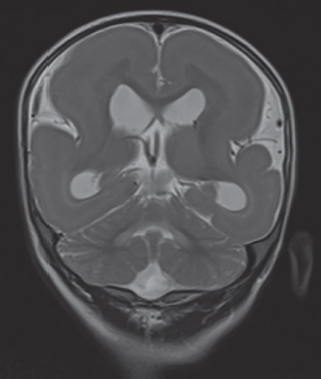

La resonancia magnética cerebral permitió reconocer un engrosamiento difuso de la corteza cerebral de forma bilateral con disminución de la superficie giral suprayacente, así como apariencia lisa de ambos hemisferios (figura 3), además se asoció con la presencia de heterotopia en banda hiperintensa en T1 e hipointensa en T2 (figura 4), así como disminución generalizada del grosor del cuerpo calloso y de ambos hipocampos (figura 5). Mediante este estudio se brindó el diagnóstico de lisencefalia de tipo 1 con heterotopia en banda del grupo IIB.

Figura 4 Secuencia T2 en corte coronal que muestra banda heterotópica hipointensa de predominio periventricular